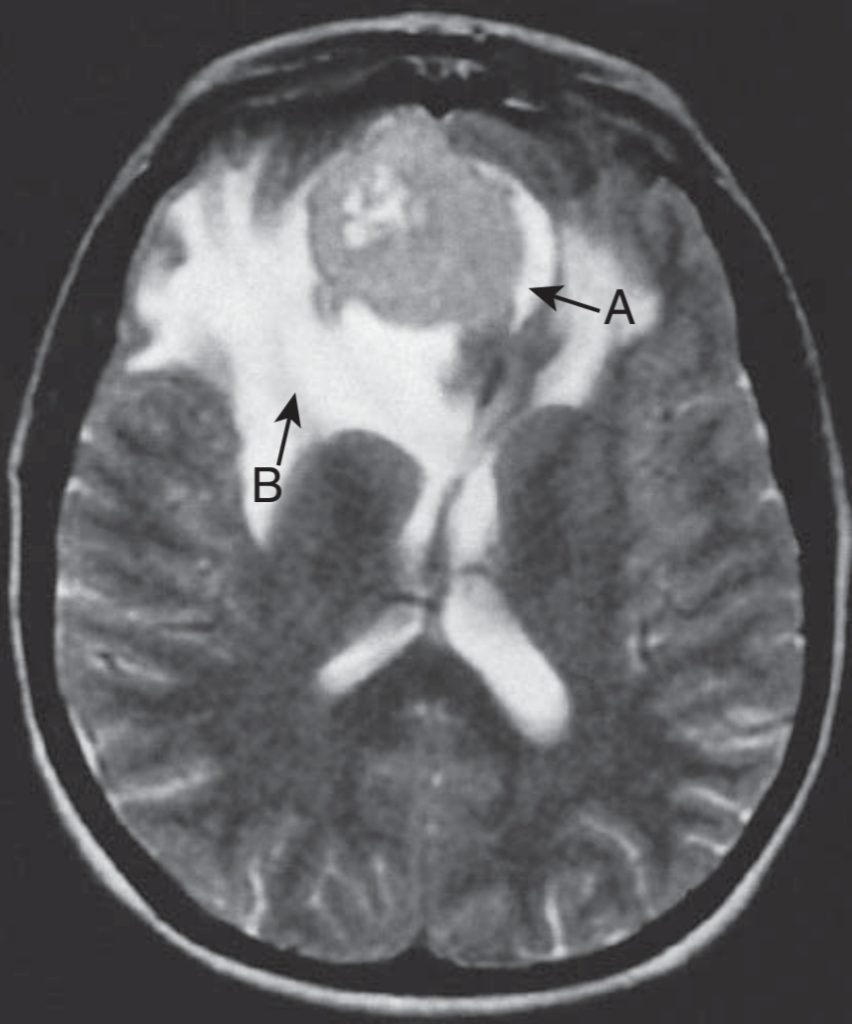

Interpretation of abnormal MRI image

Any structural abnormalities and abnormal intensities which show a change in tissue T1 or T2 weighting in term to normal grey and white matter . ( A prolonged T1 relaxation time in MRI gives hypo intensity, that is more black and a prolonged T2 relaxation time in MRI gives hyperintensity that is more white) .

Usefulness of MRI in neurological condition

MR Angiography is a procedure used to evaluate blood flow in various artery and veins in brain and spinal cord . Mainly used for aneurysms in brain and vascular malformation . Some of the MRI used for neurological condition are

- Diffusion – weighted MRI (DWI): Image based on transitional movement of water and small molecules within the brain.